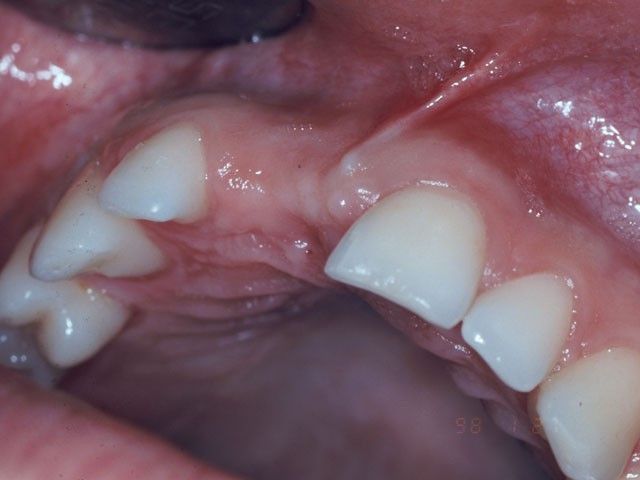

Εδώ και τριάντα χρόνια έχουμε τη δυνατότητα με τη χρήση φωτοπολυμεριζόμενων ρητινών να κάνουμε σημαντικές συντηρητικές αισθητικές αποκαταστάσεις και είκοσι χρόνια τώρα μπορούμε να τοποθετούμε όψεις και θήκες πορσελάνης χωρίς μέταλλο για την καλύτερη δυνατή απομίμηση του χρώματος των φυσικών δοντιών. Σημαντική είναι όμως και η προσφορά των μεθόδων οστικής και ιστικής αναγέννησης για την αισθητική διαχείριση την ιστών που περιβάλλουν τα δόντια.

Στη φωτογραφία η αποκατάσταση ενός άνω κεντρικού τομέα το 1997 με αισθητικά υλικά και εμφυτευματική στήριξη.